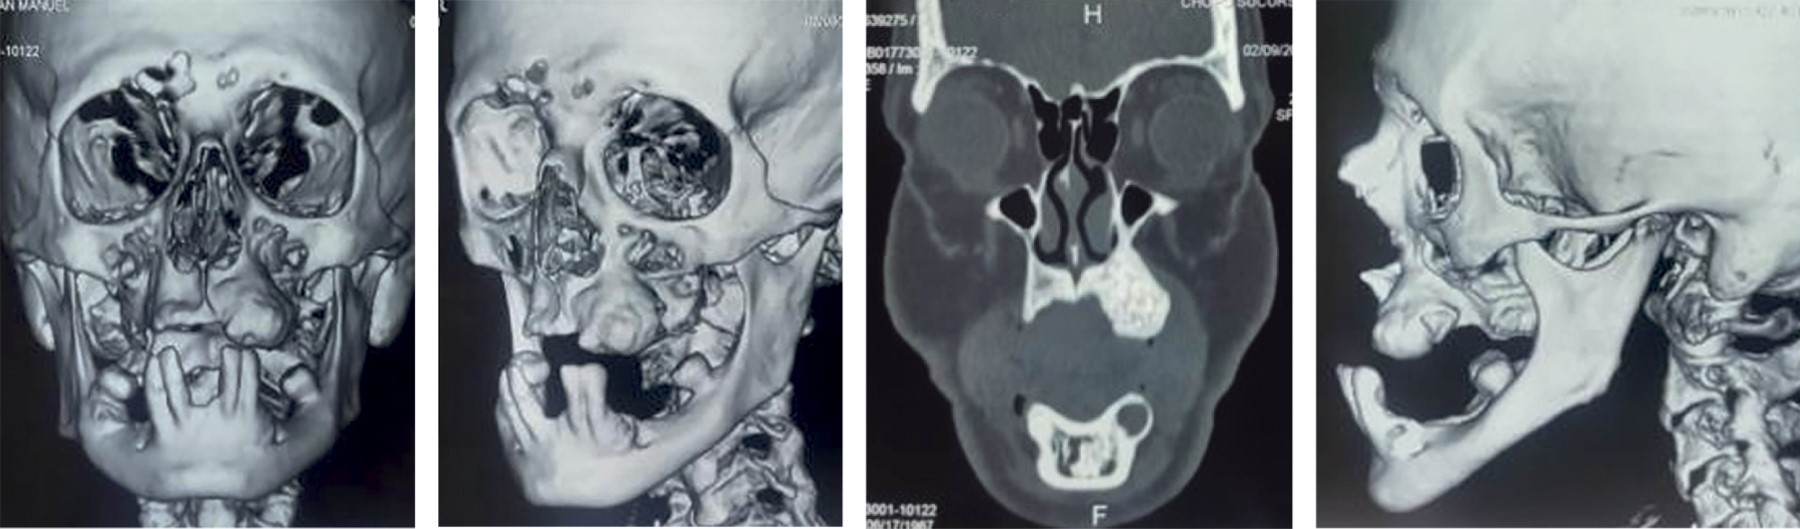

Facial tomography shows a hyperdense area in the posterior left maxillary region following the treatment for Tertiary Hyperparathyroidism, which causes severe deformity in the contour of the left maxillary alveolar process (Figure 3).

Maxillary remodeling osteoplasty is planned for subsequent prosthetic rehabilitation (Figure 4).